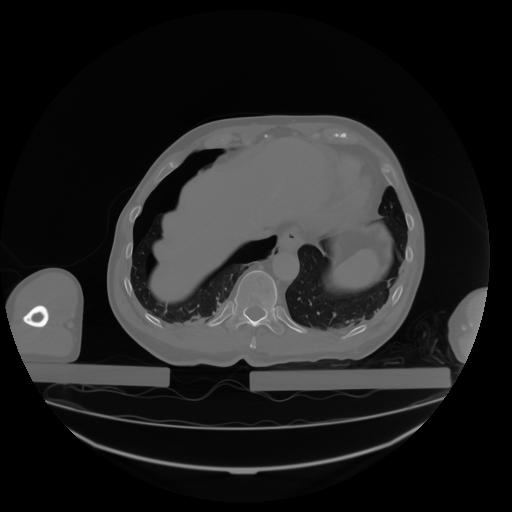

27 CUERPO,CE,Axial,3.0,CUERPO,,